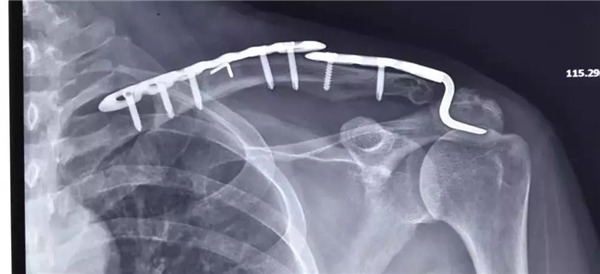

術(shù)前拍片--患者的肩鎖關(guān)節(jié)脫位屬于Rockwood  5型脫位

傳統(tǒng)手術(shù)方式——大切口上鋼板